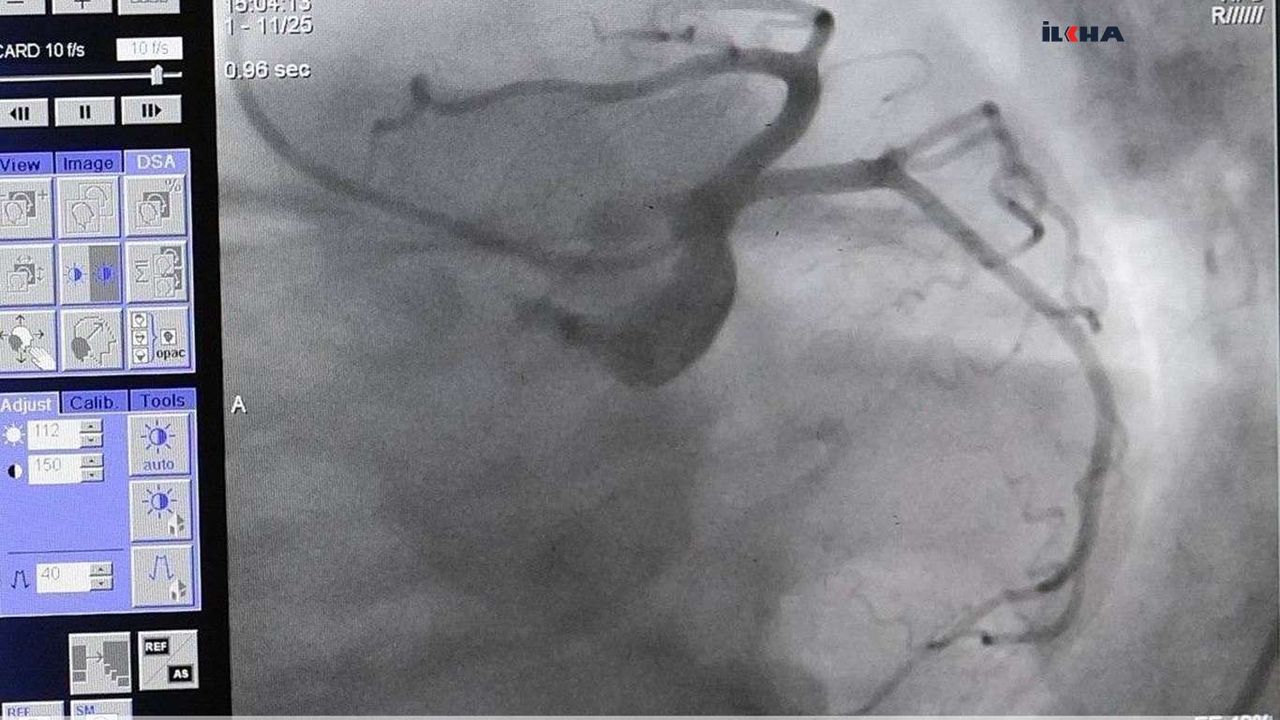

Kalp ve damar hastalıklarının bütün dünyada en sık ölüm

nedenlerinin başında geldiğini belirten Kardiyoloji Uzmanı Dr.

Gürkan İmre, bu sayının trafik kazalarından ve hatta kanserlerden daha çok

olduğunu dile getirdi.